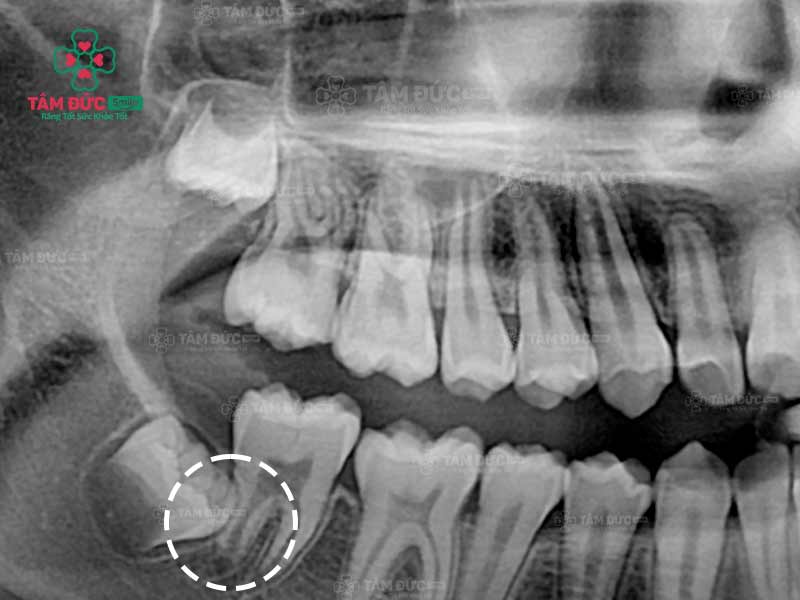

Quý khách có thể nhận biết răng khôn mọc ngầm thông qua phim chụp X-Quang

Trong quá trình di chuyển để mọc lên, răng khôn rất dễ mọc đâm vào răng số 7. Đây là dấu hiệu không rõ ràng nên Quý khách không thể nhận biết ở giai đoạn đầu. Nhưng nếu không điều trị kịp thời, răng khôn mọc ngầm sẽ gây tổn thương đến răng số 7, làm răng lung lay và dễ gãy.

Răng khôn mọc đâm vào răng số 7

Trước khi nhổ bỏ răng khôn mọc ngầm, Quý khách được bác sĩ chụp X-quang răng và thực hiện các xét nghiệm máu cần thiết. Qua phim X-Quang, bác sĩ biết được ảnh hưởng của răng đang mọc ngầm để cân nhắc phương pháp điều trị thích hợp nhất.